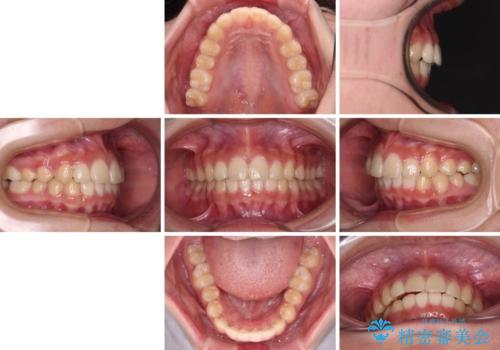

ワイヤー装置と補助装置を有効に活用し、さらには高校生ということもあり、1年9か月で狙い通りの仕上がりを達成することができました。

下の前歯が隠れてしまうほど深い咬み合わせ 高校生のインビザライン矯正治療

- 1年9ヶ月